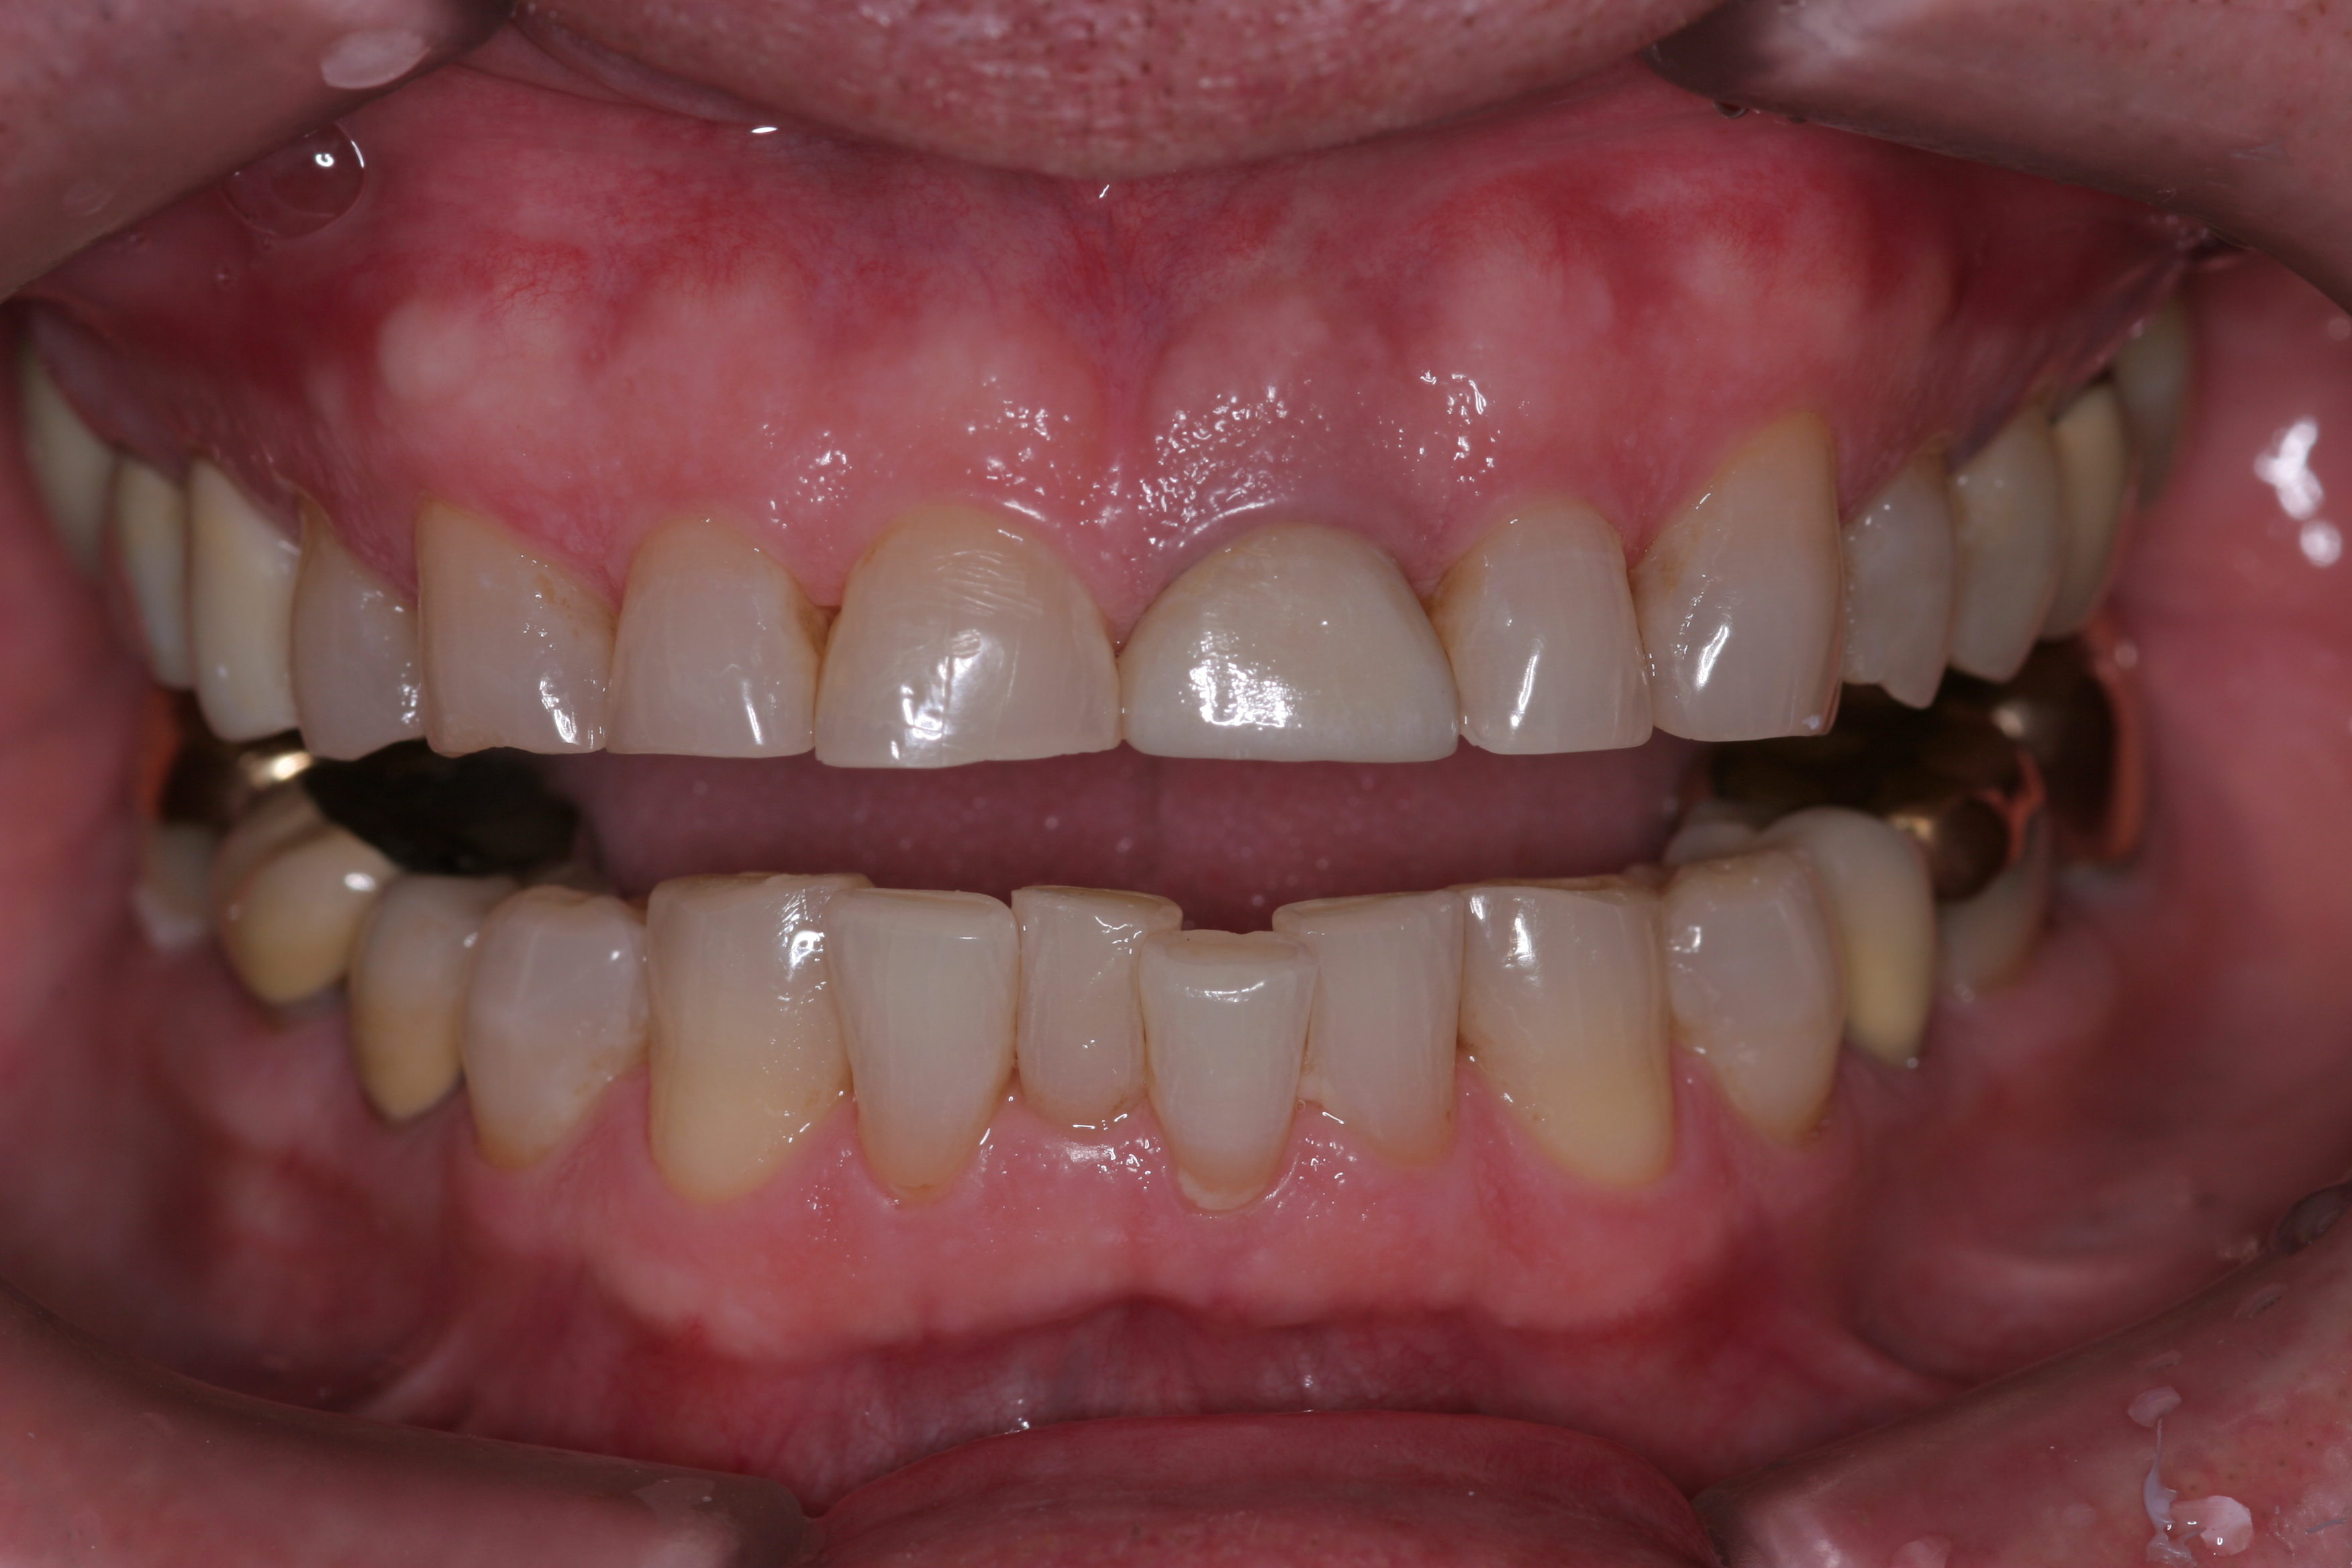

(10.) A patient presented with advanced generalized wear of her anterior teeth, and was displeased with their overall appearance because of their color and wear.

Figure 10

(11.) A patient presented with advanced generalized wear of her anterior teeth, and was displeased with their overall appearance because of their color and wear.

Figure 11

(12.) A patient presented with advanced generalized wear of her anterior teeth, and was displeased with their overall appearance because of their color and wear.

Figure 12

A patient presented with advanced generalized wear of her anterior teeth (Figure 10 and Figure 11). She was displeased with their overall appearance because of their color and wear (Figure 12). A complete examination was performed, revealing instability in her temporomandibular lateral poles bilaterally, sore muscles of mastication, advanced wear, a CR/MIP discrepancy, and loss of her anterior guidance due to the wear. Although the topic is beyond the scope of this article, the patient was also screened for possible sleep apnea. This included an evaluation of the Mallampati score, previous sleep therapy evaluation or treatment, snoring history, an evaluation of her neck size, her weight status, and the presence of the tonsils and their size. In every case, if this clinician suspects airway obstruction to be playing a role in tooth wear issues, the patient is referred to a sleep physician. The patient in this case displayed few apnea risk factors, and the patient’s anterior wear facets fit together like a “lock and key” pattern seen in parafunctional activity. Splint therapy was initiated to stabilize the joints and muscles. A repeatable CR position was verified through load testing. At this point diagnostic models, photographs, a CR bite record, and a facebow were taken and recorded.